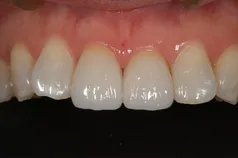

[症例]

矯正治療を行っています。

治療前は上下の歯が反対になっている所もあり、上の歯の真ん中から2本目の歯は矮小歯と言って、平均より小さな歯のため上唇が引っ込んで見えます。

インビザラインでマウスピース矯正後、オフィスホワイトニングを行い、矮小歯はラミネートベニアで修復しました。

綺麗な歯並びになるとともに、上顎の歯列のアーチが広がって、上唇がやや前方に出ることで自然な口元になりました。

- 治療期間: 1年6ヶ月

- 治療回数: 10回

- 費用: 120万円

- デメリット:治療後に矯正の後戻り防止のためのマウスピースを使用しなければならない